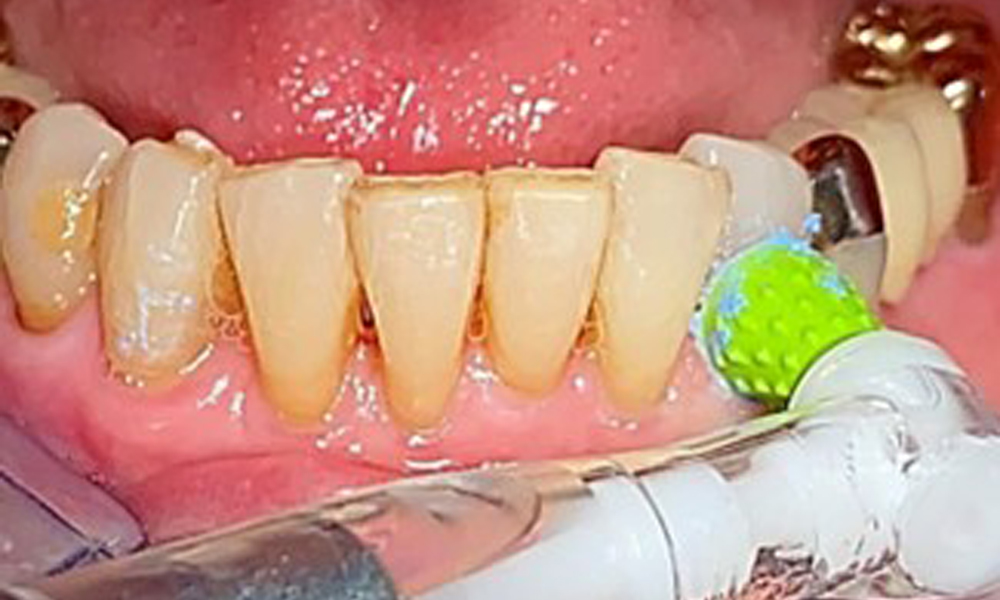

The patient was fitted with a combined removable maxillary telescopic prosthesis more than 25 years ago (Fig. 1, Fig. 2, Fig. 3) and is very happy with her dentures. The patient has an adequate fixed denture for the mandible (Fig. 4).

The patient brushes her teeth and implants three times a day with a manual toothbrush and single-tuft brush. She also uses interdental brushes once a day in the evening. She also cleans her prosthesis after every meal.

The dental findings are as follows: Combined removable implant and tooth-supported telescopic prostheses on implants 15, 13, 21, 23, 24, 25 and tooth 11 (Fig. 1, Fig. 2, Fig. 3). The patient was fitted with a fixed mandibular denture. Adequate bridges were present over 37 to 34 and 45 to 47 (Fig. 4), the crown margins were intact and there were no active caries. A composite filling with a marginal gap was present on tooth 43. There was mandibular gingival recession, exposing 1 to 3 mm of root surface. This also applies to 11.